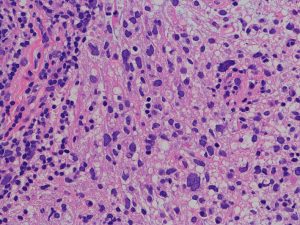

退形成性星細胞腫の病理組織

- びまん性星細胞腫と膠芽腫との中間の所見です

- 膠芽腫との違いは,腫瘍細胞が死んでいる部分(壊死 necrosis)がないことが最大の特長です

- びまん性星細胞腫との違いは,細胞核の異型性 anaplastyと分裂能の高さです,核の大きさが大小不同で歪んだ形をしています

- 画像で見えるよりかなり広範囲に広がっていて single cell infiltrationといいます

核の異型性,多核細胞が目立つ例です。グレード3の典型例です。

核異型性は乏しいのですが,細胞密度が高い例で,MIB-1染色率は12%です。グレード2と鑑別しづらいことがしばしばです。核分裂が散見されたりMIB-1染色率が高い場合はグレード3として治療をしたほうがいいでしょう。